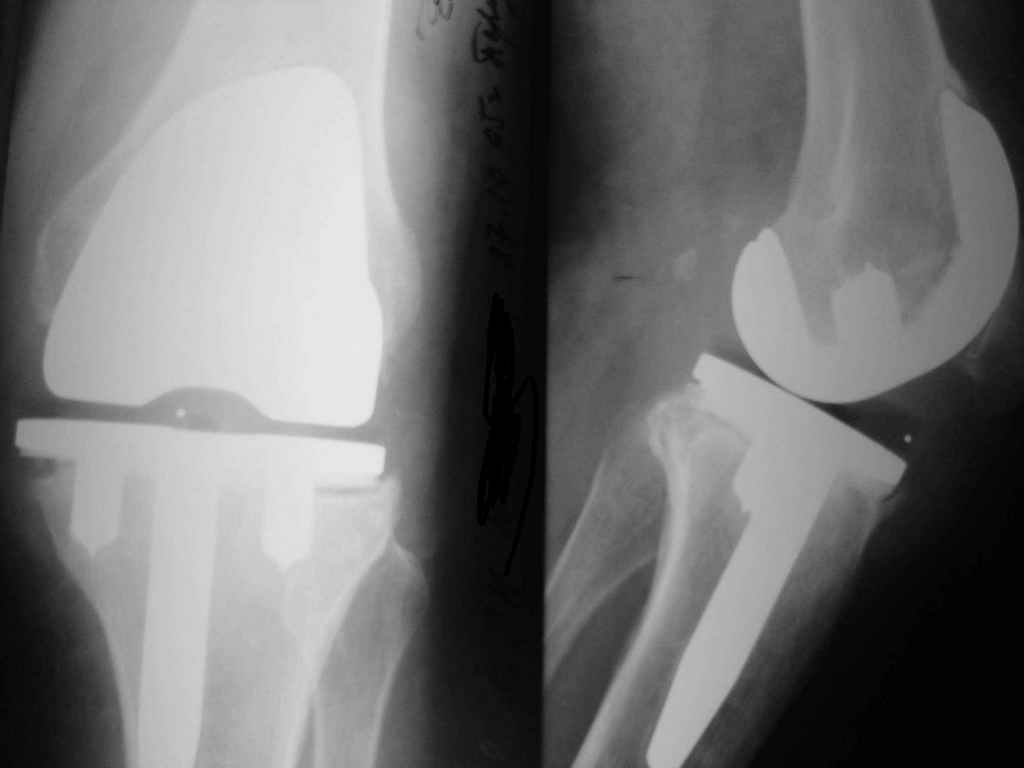

Уважаемые коллеги. Пациентка 65 лет соматически сохранна 6,5 месяцев назад выполнено замещение

коленного сустава интегральным эндопротезом Фримана Самуэльссона - цемент, по поводу ДОА.

Пункция - посев - роста не дает. Пробовали артроскопию - артрофиброз. Трудности осмотра из-за

контрактуры и спаек. Рентгенограммы в динамике - в приложении (динамика с ухудшением). Вопросы:

1. Инфекция? или остеопения местная?

2. Ревизия или подождать и полечить остеотропами?